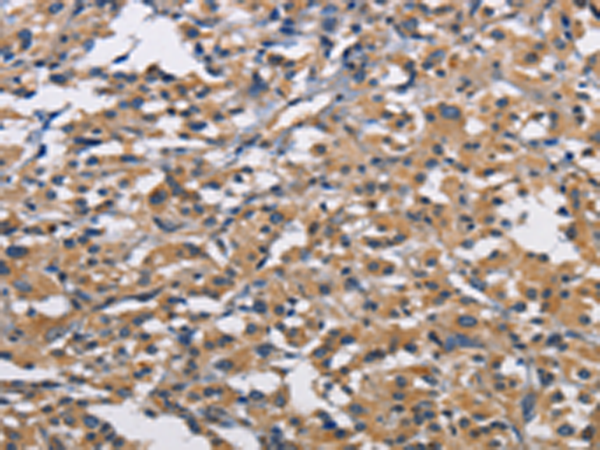

分类: 科研抗体货号: P08016别名: CBR; hCBR1; SDR21C1应用: WB,IHC反应种属: Human, Mouse, Rat